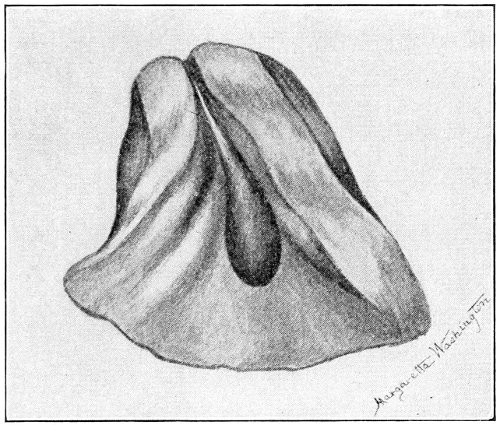

The Vaginal Speculum.—The speculum is an instrument through which a visual examination is made of the vagina, the external os uteri, and the vaginal cervix. A 29 great number of specula have been invented. At the present day the best two instruments of this class are the bivalve speculum, such as Goodell’s (Fig. 6), and the duck-bill speculum (Fig. 7), or perineal retractor, invented by Sims.

Fig. 6.—Goodell’s speculum.

Fig. 7.—Sims’ speculum.

The bivalve speculum is introduced with the woman upon her back, in the dorso-sacral position already described. The vulva and the vagina should be cleaned. The speculum should be warmed by placing it in hot water, and should then be lubricated with the soap solution or with vaseline. It should be introduced with the blades closed and the plane of the blades lying not exactly 30 in the median sagittal plane of the body, but inclined at a small acute angle to this plane, one edge of the speculum being directed toward either vaginal sulcus. The instrument is passed into the vagina toward the position in which, by a previous digital examination, the vaginal cervix had been found to lie. The instrument is then turned with the handles toward either thigh, so that the blades become parallel to the anterior and posterior vaginal walls, in order that, when separated, they will open the vaginal slit. The handles are brought together and the blades opened. When the vaginal cervix comes well into view the blades are fixed in place by the screws (Fig. 9).

Fig. 9.—Goodell’s speculum in position.

In some cases, where the cervix points well forward or well backward, it may be readily brought into view through the speculum by catching it with a tenaculum.

By means of the bivalve speculum we are able to make a partial inspection of the vaginal walls, an imperfect inspection of the vaginal vault, and a good inspection of the vaginal cervix and the external os. Applications 31 can be made to the cervix, but none of the minor operations of gynecology can be performed through this speculum.

The Sims speculum enables us to make the most thorough inspection of the vagina, the vaginal vault, and the vaginal cervix. The Sims speculum is merely a hook or retractor for the perineum, and may be introduced with the woman in the dorsal position, the Sims position, or the genu-pectoral position. If the Sims speculum is introduced in the dorso-sacral position, it is necessary to hold forward the anterior vaginal wall in order to obtain a view of the cervix.

Fig. 11.—The cervix uteri exposed with the Sims speculum.

The Sims speculum, with the woman in the dorsal, the Sims, or the knee-chest position, is the most useful instrument by which to expose the cervix uteri for any of the minor operations of gynecology. The manipulations of the operator are not hampered by working between metal walls.